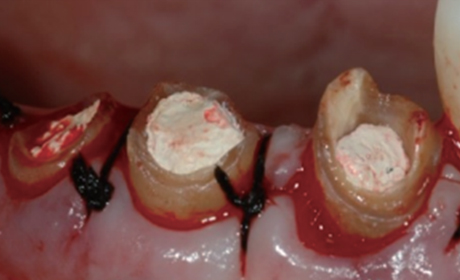

신경치료 후 남아있는 치질이 너무 짧거나 부족한 경우

크라운을 씌우기 전 치아안쪽에 기둥을 세우고 보강해주는 과정이 필요합니다.

포스트의 종류는 두가지가 있는데 사진은 기공소에서 맞춤형으로 제작된 포스트입니다.

치아의 길이가 너무 짧은 경우는 치아의 길이를 늘리는 수술이 필요하기도 합니다.